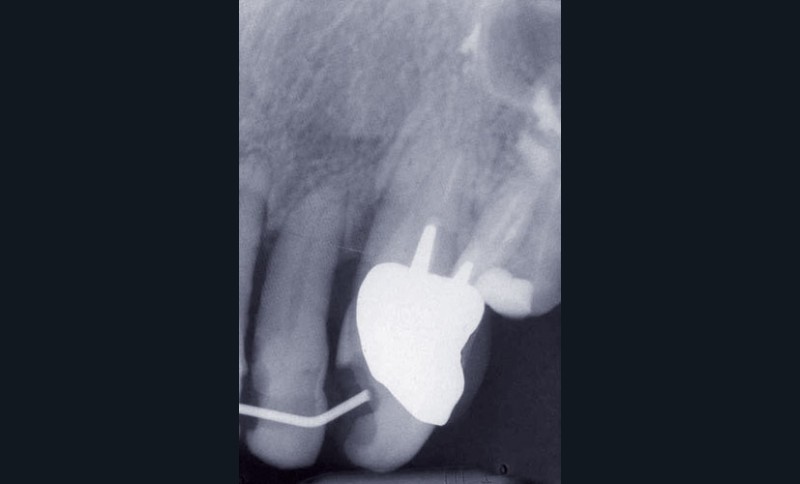

Les examens cliniques et radiographiques montrent une parodontite chronique généralisée (fig. 1a à m).

Nous décidons d’entreprendre une thérapeutique initiale parodontale classique dans tous les secteurs, y compris l’extraction de 24, un bridge de 45 à 48 avec 46 en pontique, un bridge complet de contention de 17 à 27 sur 11 piliers dentaires et une greffe épithélio-conjonctive sur 31. Cette dernière ne sera jamais réalisée. Le bridge maxillaire permettra de réduire le surplomb antérieur et d’améliorer le sourire de la patiente, ce qui constitue l’une de ses demandes.